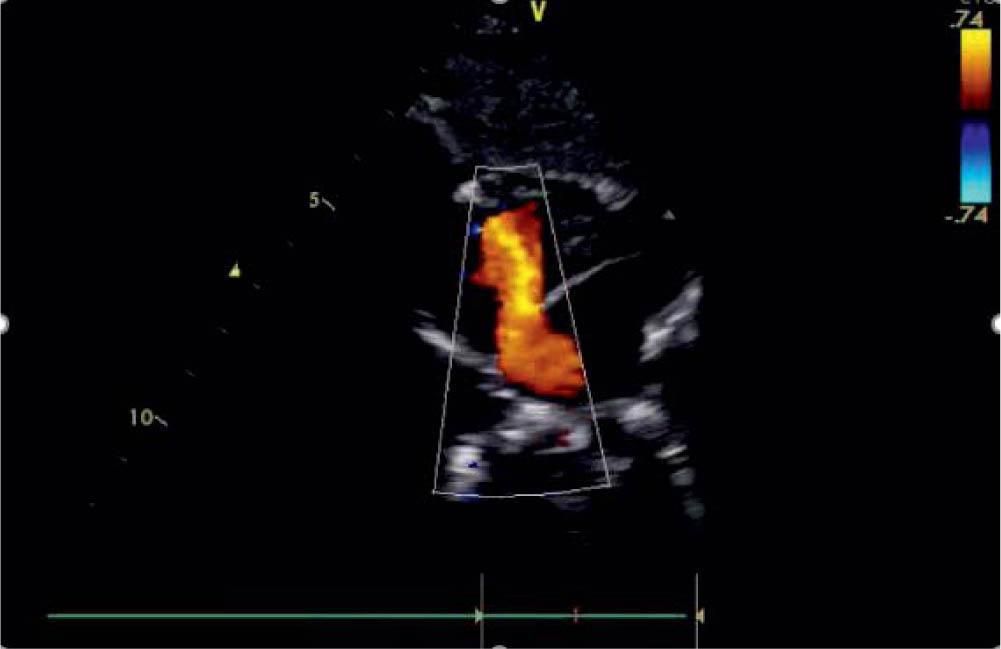

Figure 2